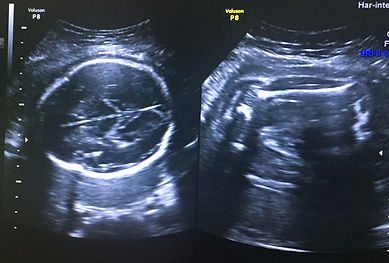

Ultrasonido Obstétrico Primer, Segundo y Tercer Trimestre. Transabdominal

Se revisa:

1. Biometría Fetal

2. Placenta

3. Líquido Amniótico

4. Cordón Umbilical